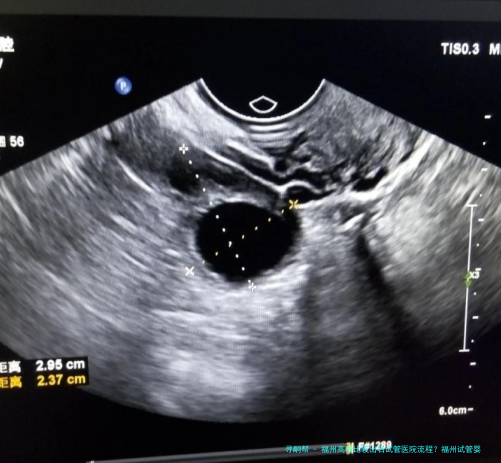

在福州三代试管婴儿医院进行高龄试管婴儿治疗前,病人须要接收诸多的体检和评估。这些检查可以帮助医生了解病人的身体状况和生育情况,为后续治疗提供准确的基础数据。常见的检查项目包括血液常规、甲状腺功能、子宫内膜厚薄程度、输卵管通顺性等。同一时刻仍旧要进行男方精液分析以确定其精子质量和数量。

福州三代试管医院针对每位患者的具体情况制定个性化的高龄试管婴儿医治策略。根据病人年纪、身体条件和生育历史等要点,医生会确定适当的促排方案,并监测激素水平和卵泡成长情形。在促排卵过程当中医生将使用无痛微小创伤技术,保障手术的安全和成功。另外福州三代试管婴儿医院还选用尖端的胚胎培养技术,提高胚胎着床率和妊娠率。